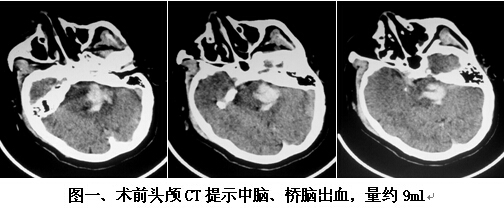

患者男,63歲,因突發(fā)神志不清2小時入院。入院時神志呈淺昏迷狀,頭顱CT提示腦干出血(橋腦、中腦區(qū)域,量約9ml)(見圖一)。神經(jīng)外科鐘三寶主任醫(yī)師查看患者后,分析患者病史、臨床表現(xiàn)及體查,結(jié)合影像學結(jié)果,考慮患者為重癥高血壓性腦干出血,需開顱行腦干血腫清除術(shù)。在發(fā)病后6小時左右,由鐘三寶主任醫(yī)師主刀,帶領(lǐng)李遠志副主任醫(yī)師為患者進行了手術(shù)。根據(jù)Brown兩點定位法則,采取枕下乙狀竇后入路,手術(shù)頭皮切口設計為勾型,骨窗大小約3cm*4cm(見圖二),術(shù)中清除腦干血腫約10ml,手術(shù)非常成功。術(shù)后復查頭顱CT提示腦干血腫基本清除(見圖三)。